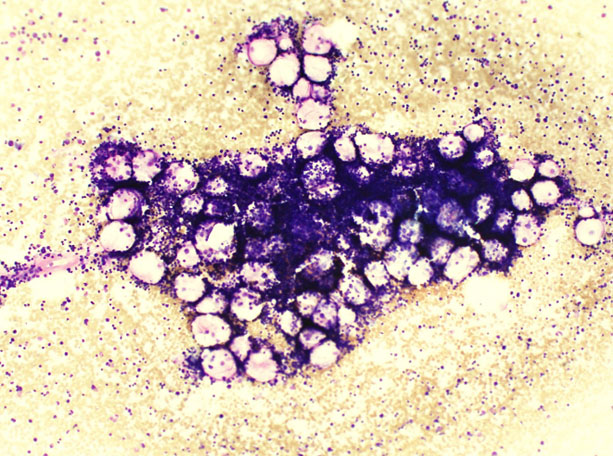

The patient succumbed on day 17 of admission without answers to her illness. The bone marrow biopsy result (Figure 5) and (Figure 6) obtained five days after the loss of patient was suggestive of hematological malignancy like MDS versus autoimmune disorders like HIV/SLE.

Figure 5: Marrow fragment which is hypocellular for the age of patient.

Figure 6: (A) Large agranular lymphoblast with cytoplasmic vacoulation, (B) myeloid cell with abnormal cytoplasmic vacoulation, (C) dysplastic monolobed neutrophil.